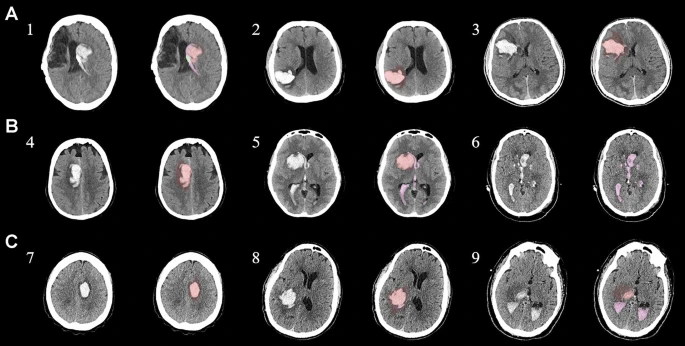

為了描述目的,患者按入組順序被賦予編號(hào),并被連續(xù)分配到三組中的一組,每組三名。根據(jù)模型2分割,ICH體積范圍為0.1至54.9mL(平均ICH體積為23.5mL)。5名ICH患者受累于局限性腦葉,其余患者受累于基底神經(jīng)節(jié)或外囊深處。3名患者的ICH位于丘腦(圖1),1名患者的血腫位于多個(gè)腦結(jié)構(gòu)(即尾狀核、殼核和蒼白球)。平均而言,MSCs是在ICH后3天注射的。